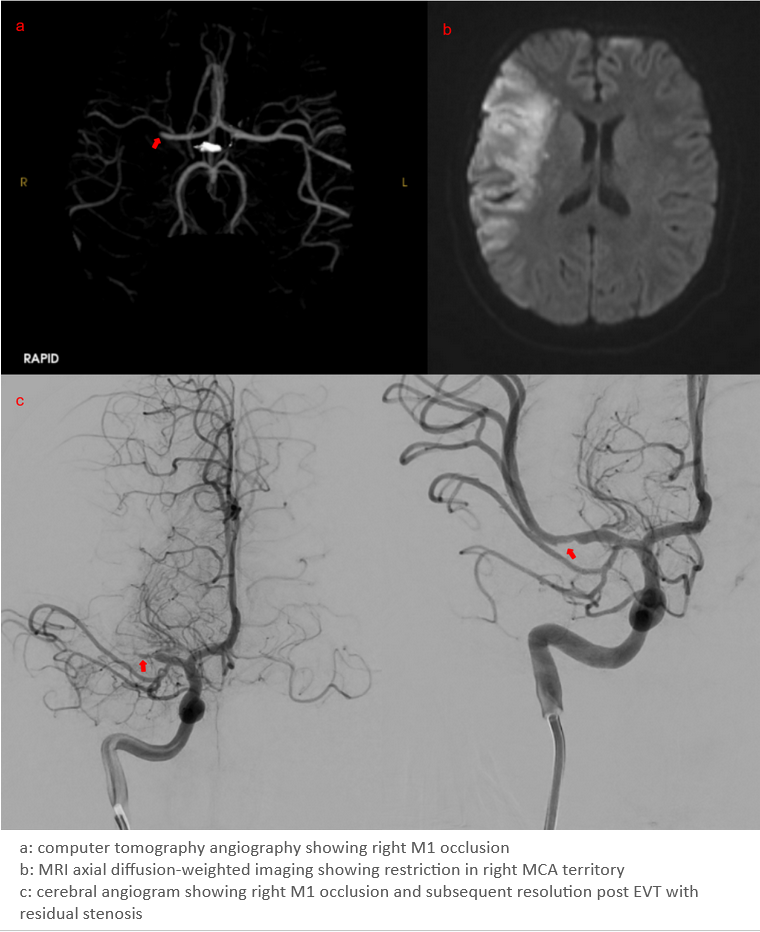

Sex differences in symptomatic intracranial hemorrhage and procedural complications after endovascular thrombectomy: Analysis of the OPTIMISE registry

Alpha Diallo

Julian Rivillas

Alexandre Poppe

Olena Bereznyakova

Richard Swartz

Grant Stotts

Jai Shankar

Nishita Singh

Jennifer Mandzia

Aristeidis Katsanos

Lily Zhou

Manraj Heran

Steve Verreault

Grégory Jacquin

Logo chum

Background

• There is heterogeneity in the literature with regards to differences in functional independence between men and women after endovascular thrombectomy (EVT) for stroke (1,2).

• Some studies suggest a lower likelihood of independence at 90 days among females, while others have found no difference when accounting for age, baseline functional independence, stroke severity and comorbidity burden (3).

• Differences in procedural complications and symptomatic intracerebral hemorrhage (sICH) between men and women after EVT is less well known.

•  This study aims to evaluate sex differences in sICH in patients who underwent EVT.

Methods

• OPTIMISE is a pan-Canadian prospective registry of patients treated with EVT across 20 sites and 7 provinces between 2018-01 and 2022-12.

• Using OPTIMISE data, we compared men and women with regards to baseline characteristics, functional outcomes and, as our primary outcomes, procedural complications and sICH

• sICH was defined  as a ≥4-point increase in the NIHSS score associated with the presence of parenchymal hematoma type 1 or 2 on follow-up CT, as determined by the treating physician

Results

3631 patients were included for analysis:

• Women were older (71.8±14.6 vs 68.0±13.1 years, p<0.001).

• There were no differences in median time from onset to puncture {232 (155-365) men vs. 235 (163-377) women, p=0.159}, and from puncture to reperfusion between sexes {(25 (17-37) vs. 24 (17-37), p=0.984}.

•  There were no differences in sICH rates {44 (2.5%) vs. 37 (2%), p=0.388}.

• Procedural complication rates were not different between men and women (5.8 vs 5.6% p=0.76)

Men

(N=1778)

Women

(N=1853)

p-value

Age (mean±SD)

68.0±13.1

71.8±14.6

0.001

Median (IQR) onset to puncture - min

232 (155-365)

235 (163-377)

0.159

Median (IQR) puncture to reperfusion - min

25 (17-37)

24 (17-37)

0.984

Tici 2b3

1446 (81.3%)

1554 (83.9%)

0.319

Tici 3

898 (50.5%)

1021 (55.1%)

0.264

sICH

44 (2.5%)

37 (2%)

0.388

Complications

• Dissection

• Perforation

• Embolization

• Arterial access

26 (1.5%)

11 (0.6%)

25 (1.4%)

45 (2.5%)

30 (1.6%)

7 (0.4%)

25 (1.3%)

43 (2.3%)

0.804

0.426

0.996

0.761

Table: Baseline characteristics in male and female

Bleeding complications in ischemic stroke3 e1619443612145

https://www.stroke-manual.com/hemorrhagic-complications-in-acute-stroke/

Conclusion

• There were similarly low and reassuring rates of sICH and procedural complications between men and women undergoing EVT in this large multicentre prospective cohort.

• Our findings complement previous studies that have demonstrated similar functional outcomes between men and women after EVT.